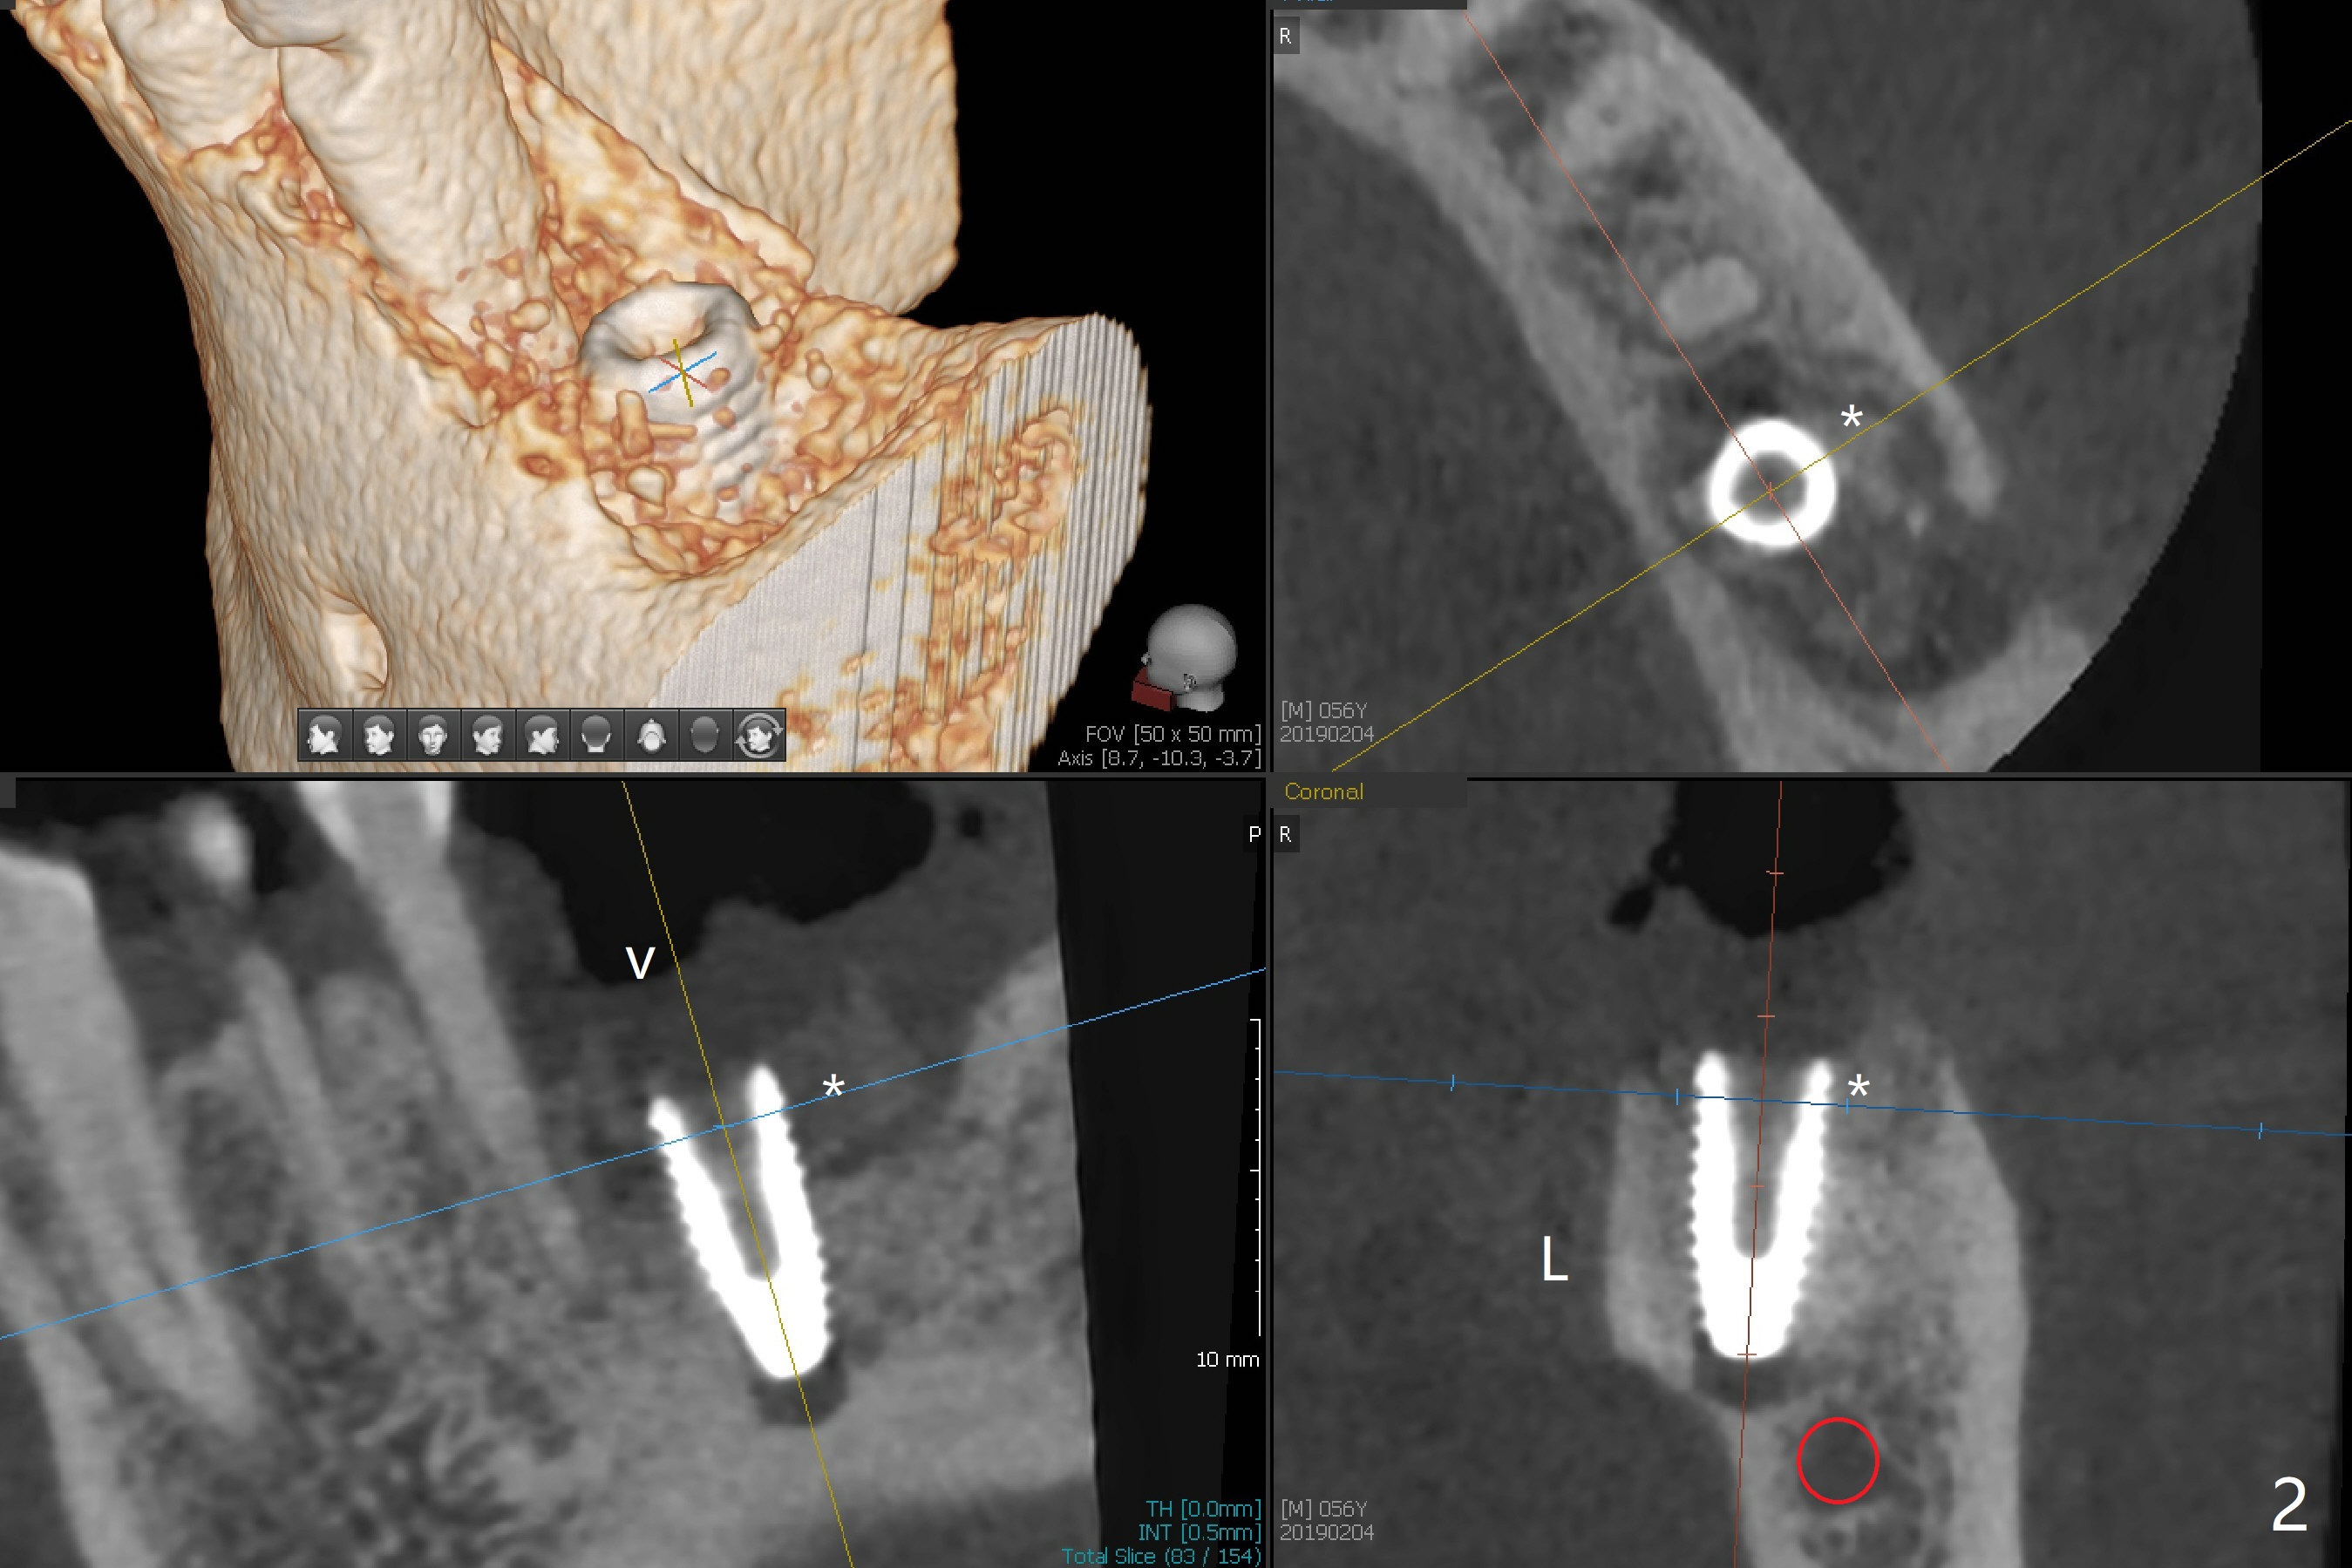

When the patient returns for #19 extraction (Fig.1), there is no 5x10 mm implant available. In fact the smaller one (4.5x10 mm) is able to achieve insertion torque >60 Ncm with more room for autogenous bone/allograft horizontally (Fig.2 *). After insertion of a definitive abutment (6.5x5.5(4) mm), more allograft is placed coronally (Fig.3 *). The gingiva that was between the mesial and distal roots before extraction (Fig.1 *) is transferred distal (Fig.4.5 *). An immediate provisional (Fig.6 P) is fabricated to close the socket opening, followed by periodontal dressing (data not shown). The latter is partially detached 2 weeks postop (Fig.7 D). When it is removed, some of possibly collagen plug is exposed distobuccally (Fig.8). When the plug is removed, some of the bone graft (Fig.9 *) is exposed distal to the provisional (P). New periodontal dressing is applied to keep the exposed graft in place. There is no apparent thread exposure 4 months postop (Fig.10). The abutment is loose 4 months post cementation, probably related to unfavorable crown/implant ratio; but when the abutment is retightened, there is a gap between it and the implant (Fig. 11 >). After relieving the proximal contact of the crown, the abutment is retightened one more time with the same gap (Fig.12 >). In fact the latter is present previously. A narrower abutment with longer cuff appears to be completely seated, probably avoiding contact with the regenerated crestal bone (Fig.13 *). If the new crown gets loose, bury a driver inside the abutment.